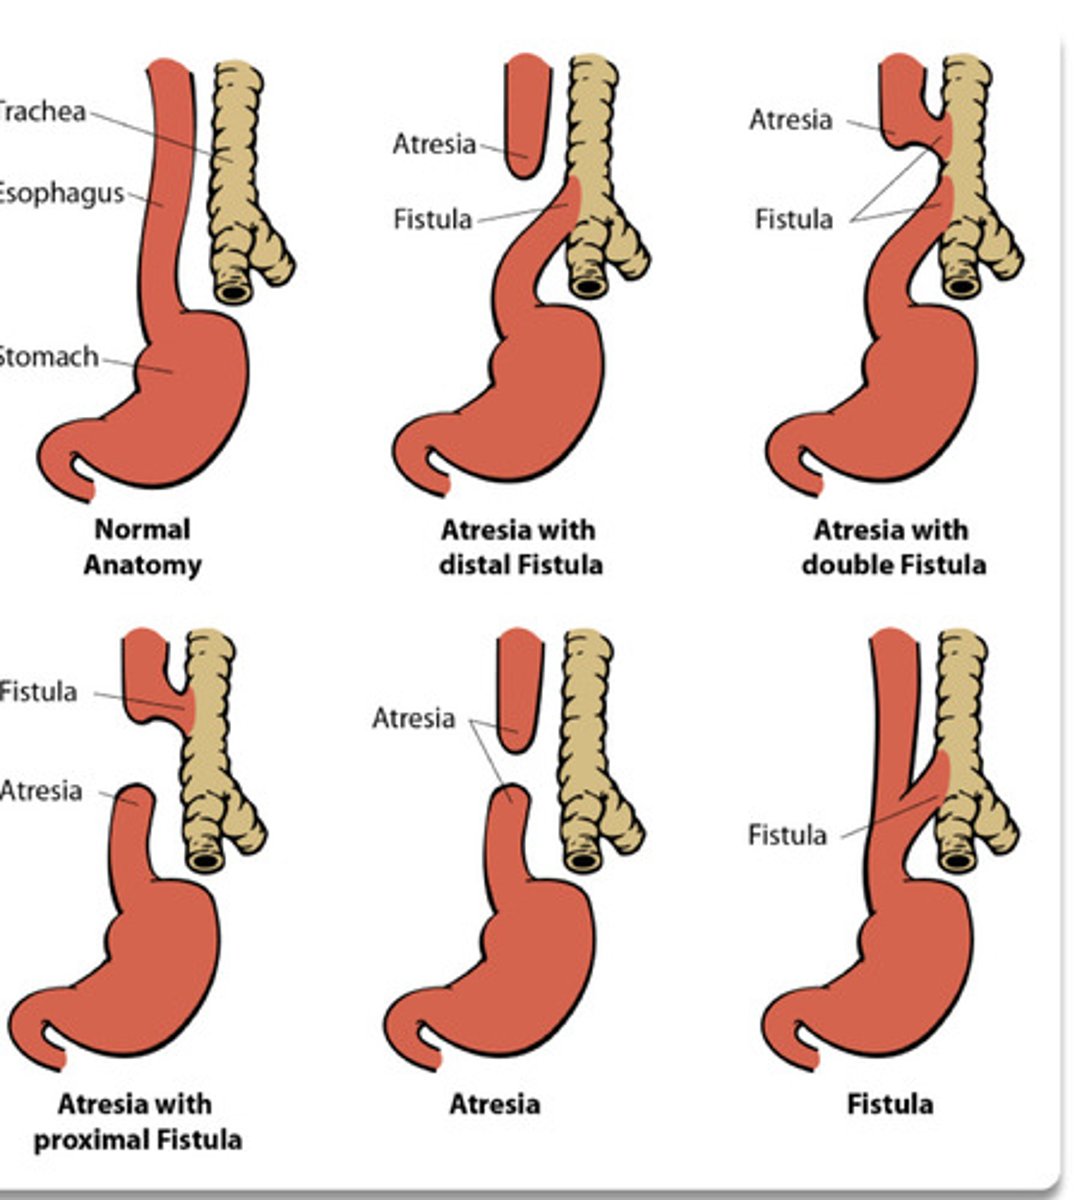

What is the most common congenital esophageal anomaly?

Esophageal atresia

What is the most common tracheoesophageal fistula?

Distal

What is a complication of esophageal atresia?

Absent peristalsis